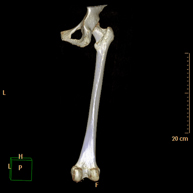

- TC d'ossos llargs Exploració radiològica que mitjançant un sistema de raigs X i detectors que giren al voltant del pacient i que reconstrueixen les imatges per ordinador (TC Multidetector), permet l'estudi detallat dels ossos llargs (tíbia, peroné, fèmur, húmer, radi i cúbit). Exploració radiològica que mitjançant un sistema de raigs X i detectors que giren al voltant del pacient i que reconstrueixen les imatges per ordinador (TC Multidetector), permet l'estudi detallat dels ossos llargs (tíbia, peroné, fèmur, húmer, radi i cúbit).